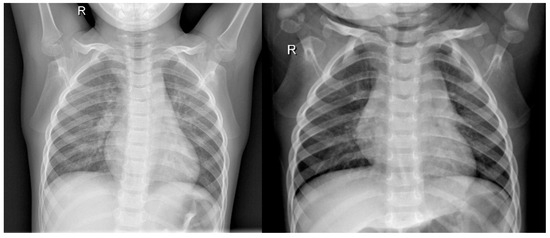

The Hurst exponent images corresponding to the cropped images in Figure 7 and Figure 8 are shown in Figure 9 and Figure 10; the second partial derivative images corresponding to the cropped images in Figure 7 and Figure 8 are shown in Figure 11 and Figure 12; and the normalized average information content images corresponding to the cropped images in Figure 7 and Figure 8 are shown in Figure 13 and Figure 14, respectively.

The results on the original dataset imply that each pre-trained model has not yet extracted all hidden features. Although use of the other three datasets will not make the results of three-stream models and four-stream models all superior to those of one-stream models, the results for all two-stream models were all superior to those of one-stream models. This can be explained according to the example images shown in Figure 7, Figure 8, Figure 9, Figure 10, Figure 11, Figure 12, Figure 13 and Figure 14, in that the original dataset presents richer information in structure, whereas the other three characteristics appear to provide simpler structural information. Therefore, we can continuously extract more hidden features from the original dataset but not from the other three characteristic datasets.

In fact, this matches our intuition that more complex models are applied to datasets with richer information or appearances, whereas simpler models are more suitable for datasets with concise information or appearance. The experimental results indicated that two-stream models have sufficient ability to extract most information from these three characteristic datasets with a simpler structure. Just as we perform feature engineering for machine learning models, we manually extracted features from the original images with a complicated structure. These extracted features generally compress high-dimensional information into low-dimensional information, and, therefore, their intrinsic structure must be simpler than that of the original image.